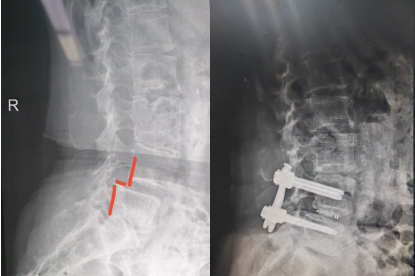

近日,苏州高新区人民医院骨科脊柱微创治疗中心,为一名61岁的女性成功实施了内镜下腰椎滑脱单边双通道脊柱内镜下椎间盘切除,椎管减压,椎间植骨融合内固定术。术后6天患者就可下地。腰疼,下肢放射疼痛症状解除,再次展示出苏州高新区人民医院脊柱外科微创手术的技术实力。

该患者半年前出现腰部及右下肢的疼痛,但休息后尚能缓解最近症状加重,身体出现侧弯,严重影响了日常生活。患者四处求医,但一直因惧怕开放手术的创伤,故一直未选择手术治疗。了解到苏州高新区人民医院一直开展的微创脊柱内镜手术,遂前来就诊,行核磁共振检查后,发现腰4椎体向前明显滑脱,椎间盘突出,椎管狭窄,压迫左侧神经根需要行腰椎滑脱椎间盘切除,椎管减压,滑脱复位,椎间植骨融合内固定手术。医院骨科脊柱微创中心刘勇主任团队为她制定了微创手术方案,腰部创面非常小。

术后患者恢复顺利,术后六天即顺利下地行走,步态正常,原腰疼和下肢疼痛,麻木症状消失,患者对手术效果非常满意。医院脊柱微创中心自2020年成立以来,依托多项微创技术,对脊柱患者尤其腰椎间盘突出症的患者进行微创手术治疗,从单纯的椎间盘突出,椎管狭窄到严重的腰椎滑脱,均可采用微创手术解除患者病痛,为此也树立了良好的口碑。